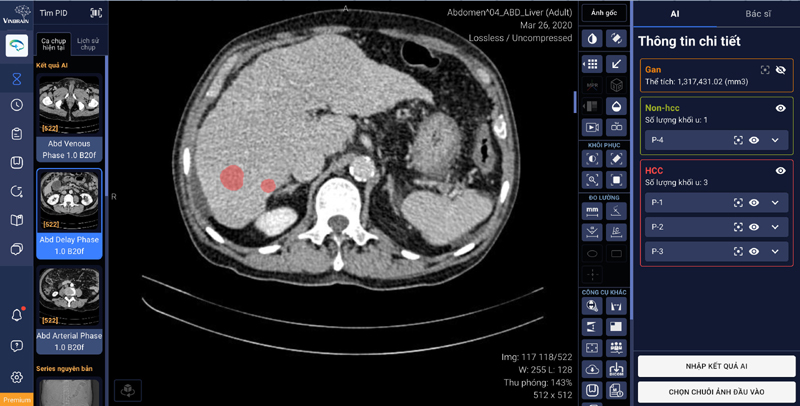

Hiện nay, chẩn đoán ung thư gan thường được thực hiện thông qua ảnh chụp cắt lớp vi tính (CT) gan đa thì, tuy vậy, ảnh CT gồm nhiều thì, nhiều lát cắt, việc trực quan hoá dữ liệu để phân tích đặc điểm y học từ ảnh CT một cách toàn diện gặp khó khăn, dẫn đến tiêu tốn nhiều thời gian của các bác sĩ chẩn đoán hình ảnh. Tính năng mới của phần mềm DrAid™ sẽ hỗ trợ tính năng tự động khoanh vùng và phân loại tổn thương gan bằng ứng dụng trí tuệ nhân tạo, kết nối trực tiếp với PACS (hệ thống lưu trữ và truyền tải hình ảnh Y tế) và trả về trên phần mềm kết quả AI khoanh vùng của gan và các tổn thương cũng như phân loại các loại tổn thương.

DrAid™ hỗ trợ tính năng tự động khoanh vùng và phân loại tổn thương gan ứng dụng trí tuệ nhân tạo, kết nối trực tiếp với phần mềm quản lý hình ảnh của bệnh viện (PACS)